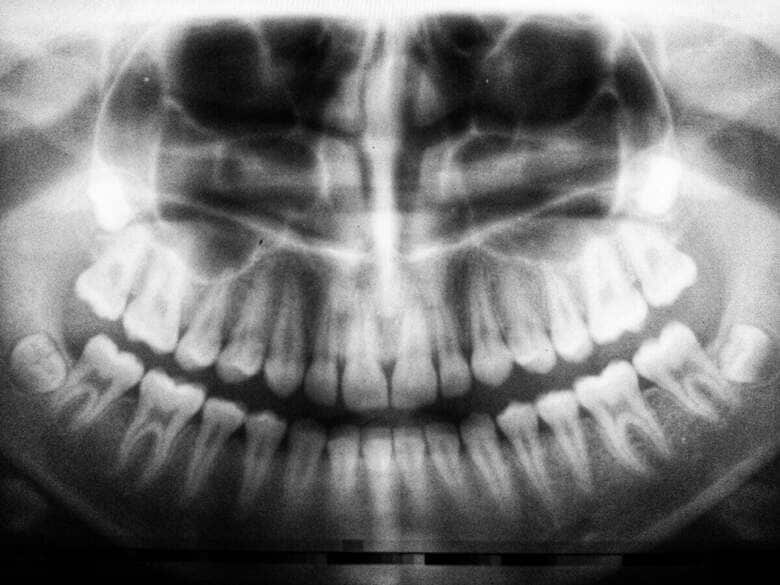

乳がん患者の口腔X線画像を映した動画がTikTokで拡散し、再生回数は500万回近くに達している。

動画を投稿したのは、ユタ州を拠点とする歯科医で、ホリスティック・ヘルス(※)の認定専門家でもあるミシェル・ジョーゲンセン医師(@livingwellwithdrmichelle)。彼女は乳がんを患っているメリッサ・ジェイコブセンの歯のスキャン画像を共有した。

ジョーゲンセンは、過去に根管治療を受けた歯が2本、内部で細菌感染を起こしていたため抜歯した、と説明し、本誌に次のように語った。

「感染した歯ががんを引き起こすわけではありませんが、体ががんと闘う力を著しく弱めてしまう可能性があります」

歯の下に「黒く大きな空洞」